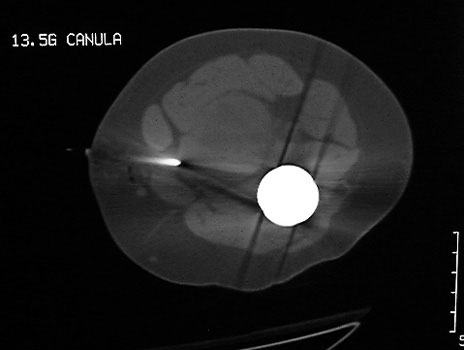

Dislocated femoral component and acetabular cup in grossly loose arthroplasty.  CT guided aspiration to rule out infection.

CT guided biopsy